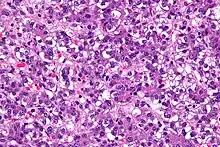

| Micrograph of a hepatoblastoma. H&E stain. | |